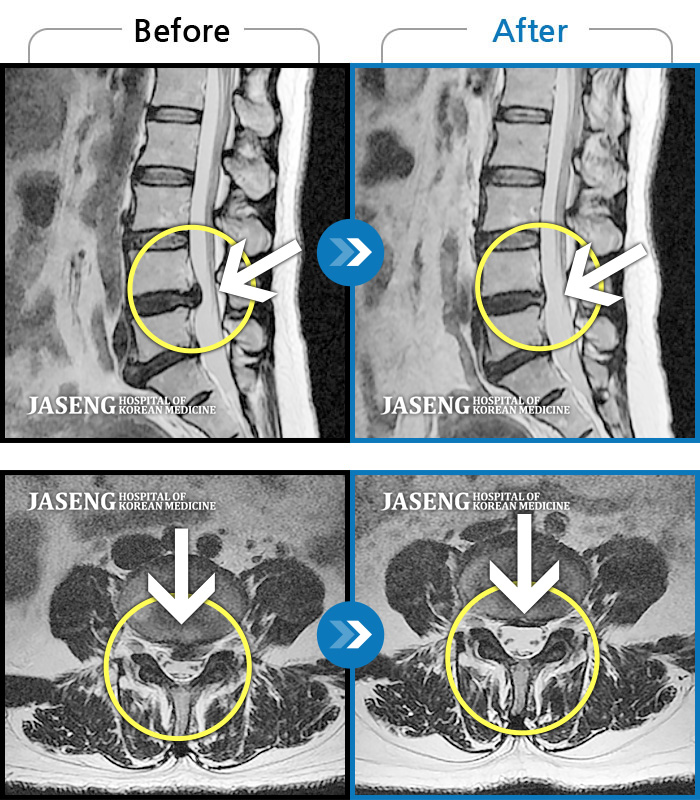

Before

After

환자에게 사전 동의를 받아 동일 조건에서 촬영되었습니다.

개인에 따라 치료 후 부작용이 발생할 수 있으니 의료진과 상담 후 치료를 진행하시기 바랍니다.

좌측 허리와 골반에 통증, 좌측 다리에 통증과 저림

허리 통증, 우측 종아리 외측으로 당기고 저림